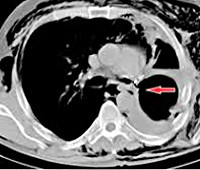

• Рентгенография, КТ грудной полости. В раннем послеоперационном периоде рентген и компьютерные томограммы могут обнаружить смещение или отсутствие скоб из тантала, используемых при механическом сшивании раны. Позднее появляются признаки пневмоторакса, гидроторакса с горизонтальным уровнем. Чтобы выяснить местоположение отверстия, иногда используется бронхография.